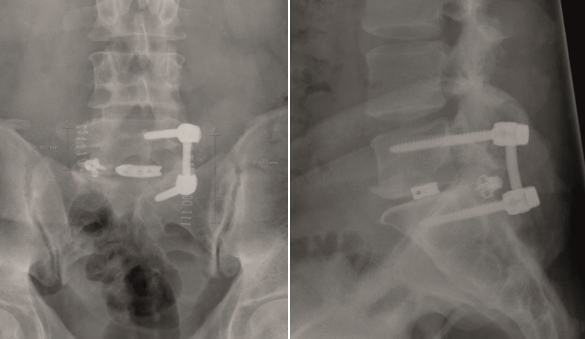

Multilevel facet pathology is shown in Fig 6. Intraoperative and postoperative images are shown (Fig 7-9).